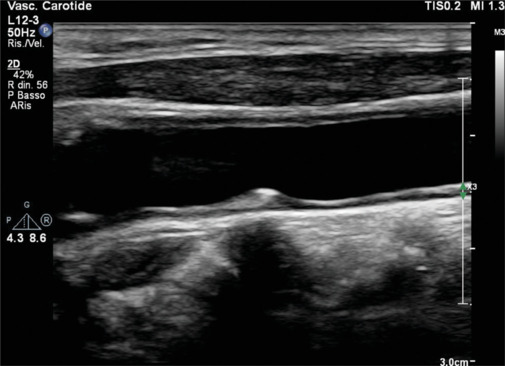

心血管疾病(cvd)仍然是世界范围内发病率和死亡率的主要原因,传统的预防措施侧重于改变生活方式、药物干预和风险分层。最近,成像已经成为心血管预防的一种有趣的工具。这篇综述探讨了各种成像方式在早期发现、风险评估和疾病监测中的作用。无创技术,如颈动脉超声、动脉硬度评估、超声心动图和冠状动脉钙评分,可以识别亚临床动脉粥样硬化和心室功能障碍,提供补充传统危险因素的见解。冠状动脉计算机断层血管造影和心脏磁共振提供血管和心肌病理的高分辨率可视化,有助于精确的风险分层。此外,心外膜脂肪组织和肝脂肪变性等新兴标志物正逐渐被认为是心血管风险的潜在预测因素。人工智能(AI)的进步通过增强图像解释、自动化风险预测和促进个性化医疗,正在彻底改变心血管成像。未来的研究应侧重于优化影像学与临床工作流程的整合,改进风险预测模型,探索人工智能驱动的创新。通过利用成像技术,临床医生可以加强一级和二级预防策略,最终减轻心血管疾病的全球负担。

Cardiovascular diseases (CVDs) remain the leading cause of morbidity and mortality worldwide, and traditional preventive measures focus on lifestyle modifications, pharmacologic interventions, and risk stratification. Recently, imaging has emerged as an interesting tool in cardiovascular prevention. This review explores the role of various imaging modalities in early detection, risk assessment, and disease monitoring. Noninvasive techniques such as carotid ultrasound, arterial stiffness assessment, echocardiography, and coronary artery calcium scoring enable the identification of subclinical atherosclerosis and ventricular dysfunction, providing insights that complement conventional risk factors. Coronary computed tomography angiography and cardiac magnetic resonance offer high-resolution visualization of vascular and myocardial pathology, contributing to refined risk stratification. Furthermore, emerging markers such as epicardial adipose tissue and hepatic steatosis are gaining recognition as potential predictors of cardiovascular risk. Advancements in artificial intelligence (AI) are revolutionizing cardiovascular imaging by enhancing image interpretation, automating risk prediction, and facilitating personalized medicine. Future research should focus on optimizing the integration of imaging into clinical workflows, improving risk prediction models, and exploring AI-driven innovations. By exploiting imaging technologies, clinicians could enhance primary and secondary prevention strategies, ultimately reducing the global burden of CVDs.